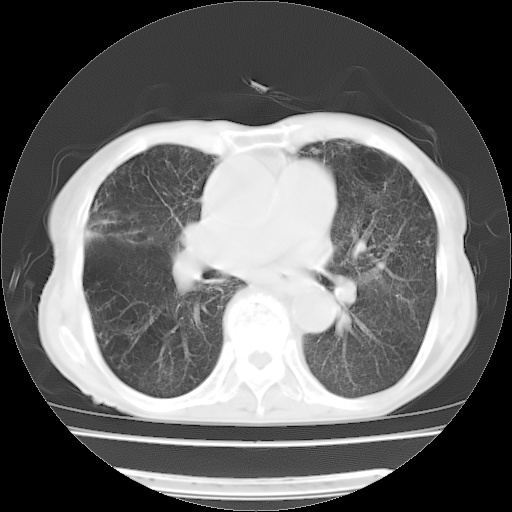

病人发热、气促就诊。原二周前已行ct扫描,当时诊断为双肺下叶、右肺中叶支气管扩张并感染,双肺上叶片状渗出性病变。今天复查胸部ct,双肺下叶支气管扩张并感染病灶较前明显吸收,但双肺上叶渗出性病变较范围较前明显增大。

双肺多发大片状、斑片状高密度渗出影,部分实变,考虑病毒性肺炎。